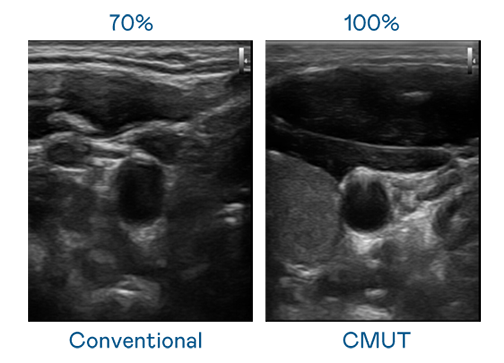

CMUT 技術是一種用電容式微機電元件來產生超音波訊號的技術。與傳統 PZT 壓電式技術相比,CMUT 頻寬增加 30%,更寬頻的超音波訊號讓影像解析度大幅提升,是實現高影像品質醫療超音波掃描、促進精準醫療發展的關鍵技術。

超音波影像的解析度高低,首先取決於探頭能發出的訊號頻寬。JJB竞技宝 CMUT 可提供高清晰的超音波訊號,提供高頻寬、高靈敏度、影像紋理細節更高的超音波影像,協助醫護人員縮短影像判讀時間及利用精準的醫療影像進行診斷。